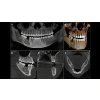

ORTHOPHOS SL 3D

Dentsply Sirona

Revoluční technologie, patentované řešení pro polohování a extrémně všestranné funkce 2D / 3D hybridní jednotky Cena na vyžádání Získejte 50% dotaci z EU na digitalizaci praxe